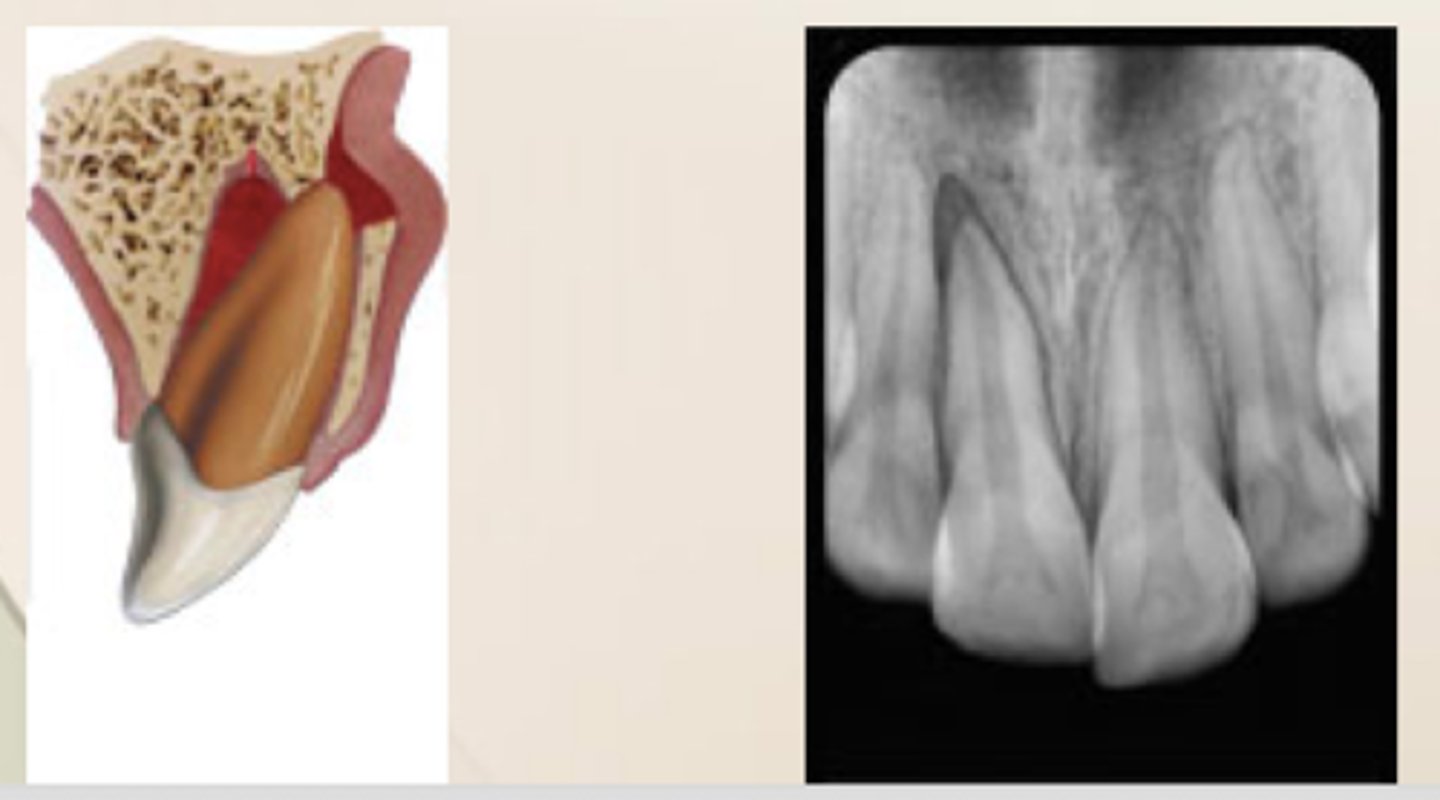

Root Fracture

coronal fragment may be mobile and may be displaced

occlusal interference may be present

What is the poorest prognosis for root fracture?

coronal

_% of primary tooth injuries are rooth fractures

2-4%

___% of teeth with root fracture exhibited pulpal necrosis

9.4%

___% of teeth with root fracture exhibited pulp obliteration

9.2%

Root fractures are usually the ___ to -__

middle to apical 1/3